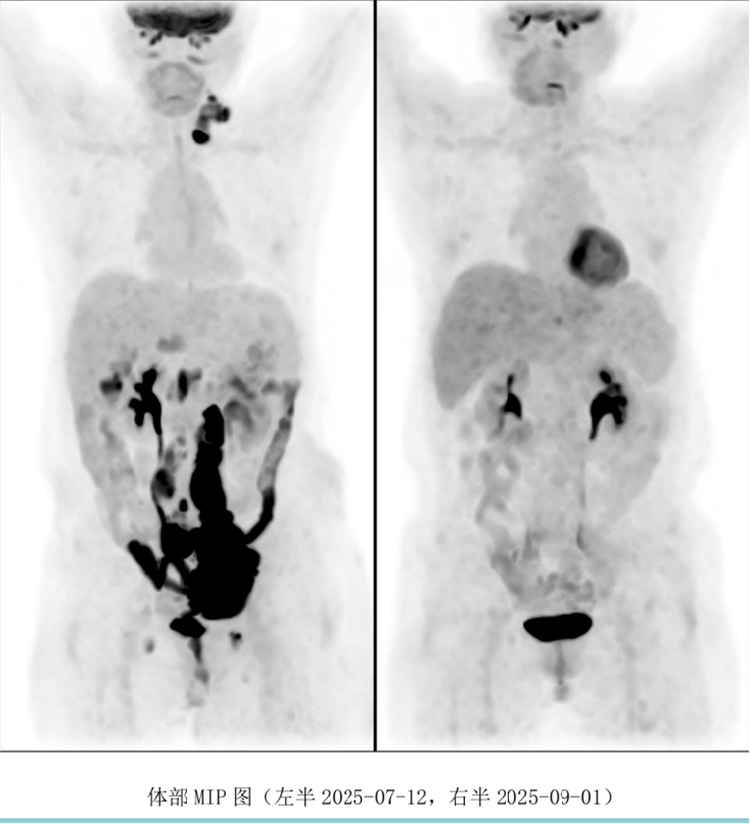

病例汇报环节由我院淋巴瘤科张薇医生带来了三例精彩纷呈的难治复发弥漫大B淋巴瘤CAR-T治疗的病例。

病例过程跌宕起伏,从桥接治疗到靶点的选择,并发症的处理都极具代表性。张医生详尽分享了患者在治疗过程中的挑战、决策依据以及CAR-T细胞治疗后的惊人缓解与转归,充分展示了CAR-T技术为晚期患者带来的突破性生存希望。